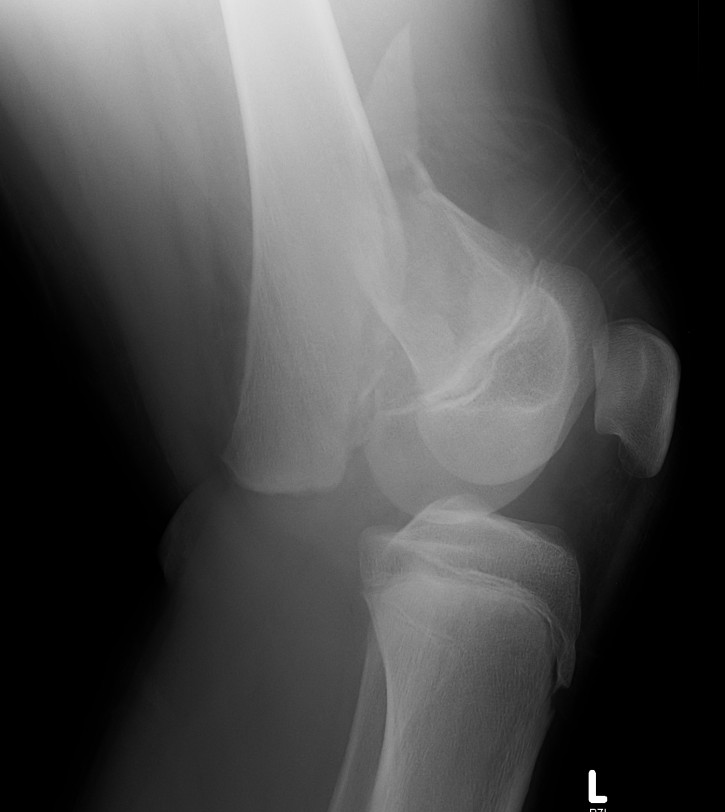

Salter Harris I

Salter Harris II

Displaced

MUA +/- ORIF

Low threshold to ORIF to maintain position

- already have high risk of growth arrest / LLD / angular deformity

- don't wish to deal with malunion / loss of position as well